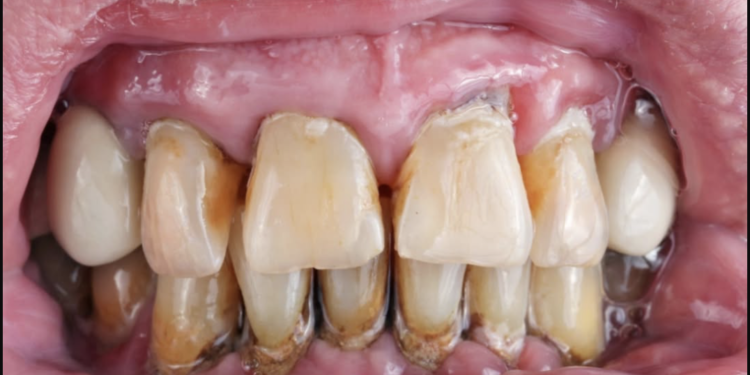

Sipas studimit, personat me më shumë dhëmbë të humbur apo të dëmtuar rezultojnë të kenë një rrezik më të lartë për të vdekur më herët, ndërsa ata me dhëmbë të shëndetshëm ose të trajtuar kanë një probabilitet më të ulët.

Studiuesit theksojnë se jo vetëm dhëmbët natyralë, por edhe ata të trajtuar apo të mbushur, konsiderohen faktor pozitiv në parashikimin e jetëgjatësisë.

Një nga arsyet kryesore lidhet me faktin se problemet dentare mund të shkaktojnë inflamacion kronik, i cili lidhet me sëmundje serioze si ato kardiovaskulare apo diabeti.

Gjithashtu, mungesa e dhëmbëve ndikon në ushqyerje, pasi individët kanë më shumë vështirësi në përtypje dhe shpesh orientohen drejt ushqimeve më të buta, por më pak ushqyese.